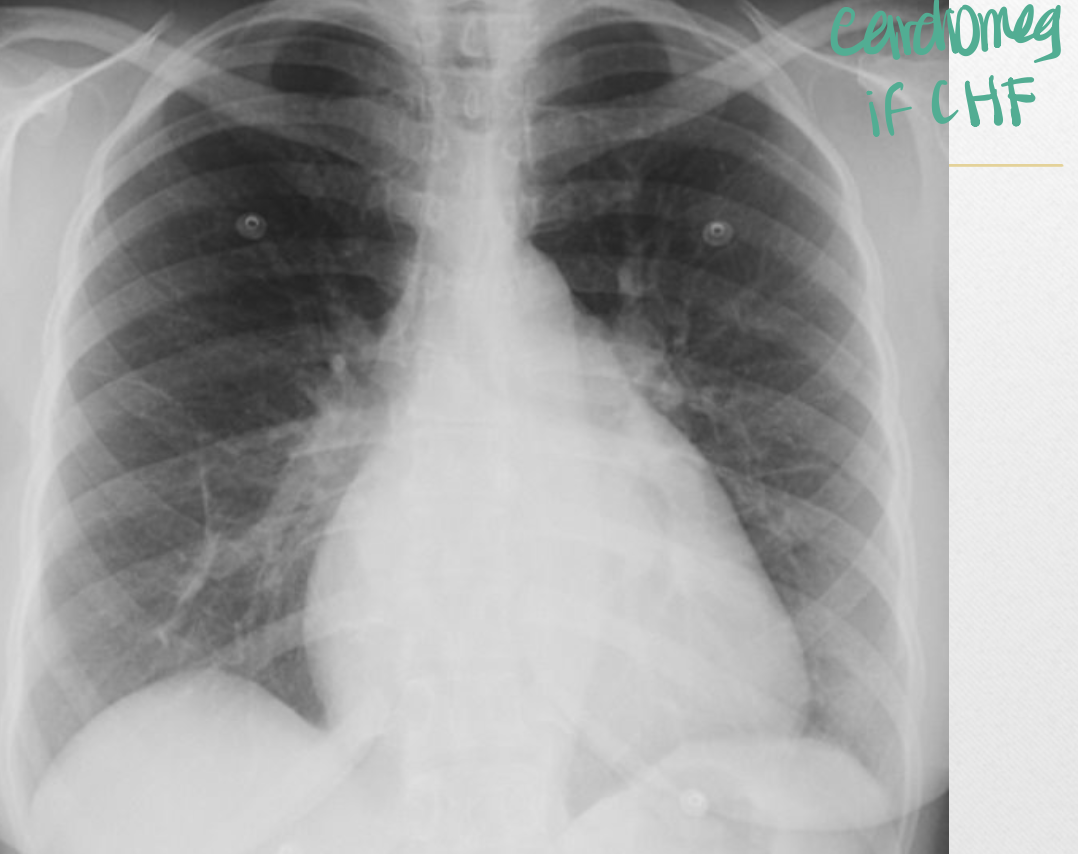

What can be shown on CXR of MS?

A